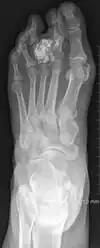

![]() | |

| Osteochondroma, a common type of non-cancerous chondrogenic tumors | |